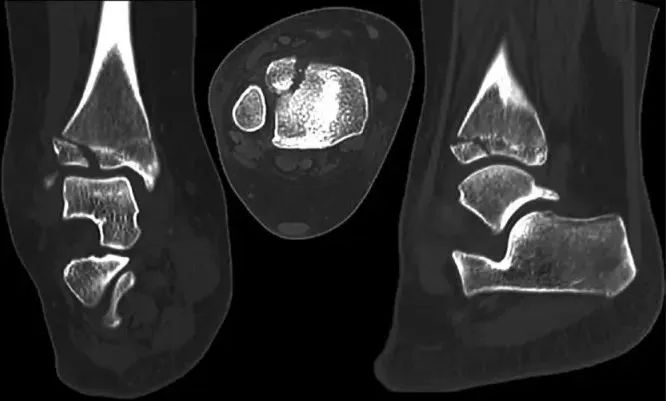

辅助检查上,由于Tillaux骨折片较小、X线片上有胫骨的遮挡以及临床医生认识不足,所以很容易被漏诊。一般来说,正位、侧位和踝穴位 X 片可发现移位超过 2 mm 的 Tillaux 骨折(在踝关节 X 片显示为 Salter-Harris III 型);但如果移位不大,X 片就极易漏诊。临床上对怀疑有该部位损伤时,应摄踝关节内旋30°~45°斜位X线片和CT片,CT 是评估 Tillaux 骨折及其移位程度的最佳术前手段,评估移位不大的 Tillaux 骨折更敏感。